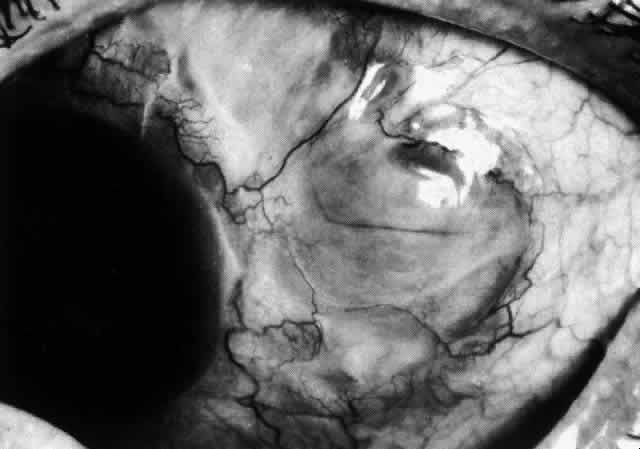

In contrast to simple episcleritis, the infiltration and edema of nodular episcleritis are localized to one part of the globe, forming a nodule and some surrounding congestion (Color Plate 1B). The nodule can be moved over the underlying sclera, which is not edematous. The scleral plexus of vessels can be distinguished deep to the nodule, lying flat on the sclera and slightly congested but otherwise normal in color and configuration (Figs. 15 and 16). Episcleral nodules may be single or multiple but do not undergo necrosis (see Fig. 16). After multiple attacks of nodular episcleritis in the same location, the superficial lamellae of the sclera show some alteration and become slightly more transparent in this one area.

Fig. 16. Deep vessels, which are normal in configuration, can be traced beneath edematous nodules lying flat on the sclera. (Watson PG: Connective tissue disorders and the eye. In: Recent Advances in Ophthalmology, Vol 5, pp 214–277. London, Churchill-Livingstone, 1975)